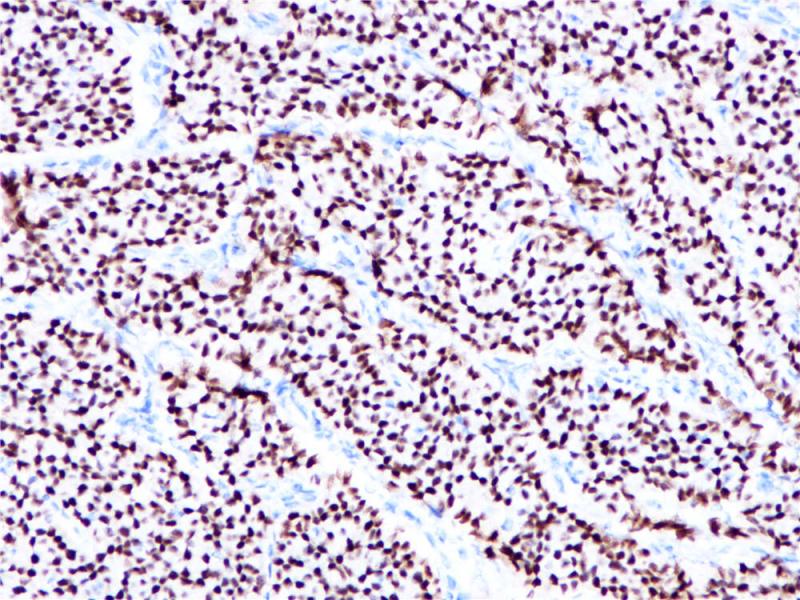

Estrogen Receptor α 重组兔单克隆抗体

雌激素受体(ER)属于核受体超家族的类固醇受体,由553个氨基酸组成。雌激素受体分子具有三个结构域,即DNA结合中央结构域,C末端的激素结合结构域和N末端的转录激活结构域。ER参与女性性激素的调节功能,主要是17(E2),在一些目标组织的生长、分化和功能方面,如女性和男性生殖道,乳腺,骨骼和心血管系统。ER α存在于正常乳腺和子宫内膜组织的上皮细胞的细胞核,以及乳腺癌的亚型中。其次, ER α可作为一个肿瘤标志物,与抗孕酮受体的抗体组合,可用于腺癌的分类。

阳性对照

乳腺癌

亚细胞定位

细胞核